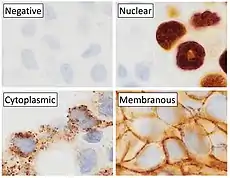

p63 immunostaining has utility for head and neck squamous cell carcinomas, differentiating prostatic adenocarcinoma (the most common type of prostate cancer) and benign prostatic tissue;[23] the nuclei of the basal cells of normal prostatic glands stain with p63, while the malignant glands in prostatic adenocarcinoma (which lacks these cells) do not.[24] P63 is also helpful in distinguishing poorly differentiated squamous cell carcinoma from small cell carcinoma or adenocarcinoma. P63 should be strongly stained in poorly differentiated squamous cell, but negative in small cell or adenocarcinoma.[25]

Cytoplasmic staining on immunohistochemistry is seen in cells with muscle differentiation.[26]